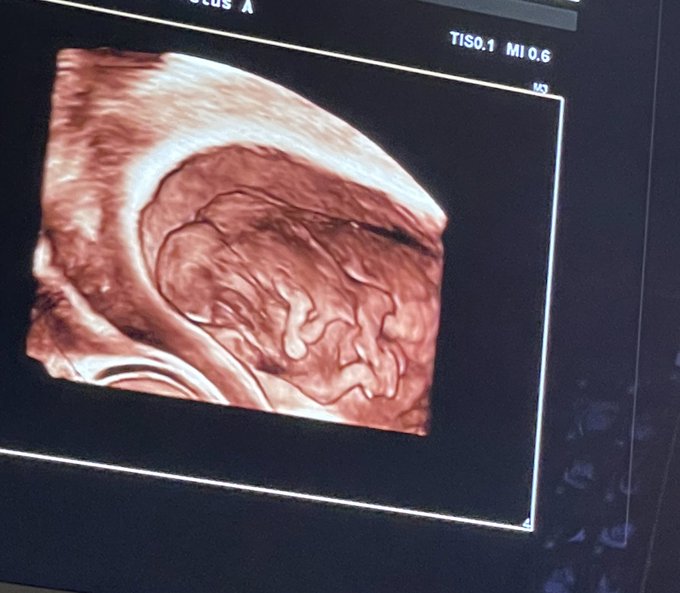

Then, at 10 weeks, Nicole experienced such intense pain in her abdomen that she went to the emergency room at 2:00 in the morning. It was there that she and Austin learned they were having twins — but that the twins were conjoined.

“The technician said, ‘You’re having twins’ and I started crying,” she said. “I was so happy and so excited. ‘But your twins are very, very special because they are conjoined twins and they share one heart and one liver.’ And I was just in complete shock. I was just crying because I knew that they were going to die. I just knew — because how can one heart be shared for two people?”

The following day, a more extensive ultrasound was carried out, revealing that the girls shared a heart, a liver, a diaphragm, bowels, and one umbilical cord in one gestational sac. They also showed signs of having chromosomal abnormalities. The doctors told Nicole and Austin that the pregnancy was not viable, and the chances of miscarriage were even greater than the chances of survival. They asked the couple if they wanted an abortion.

“So I said, ‘What’s the point of getting an abortion? We are completely against abortion. … This is not what we’re going to do,'” she explained. During the ultrasound, the babies had been jumping in sync with each other. Austin told her, “Look at our babies. They are alive. They are human and they are fine.”

At 20 weeks, the twins underwent a fetal echocardiogram, and it was determined that the heart they share has four chambers, but two left aortas. Nicole returns to the hospital every two to three weeks to check the twins for signs of heart failure, and to make sure the fluid and placenta are good, and so far, they have been doing well and continue to grow.